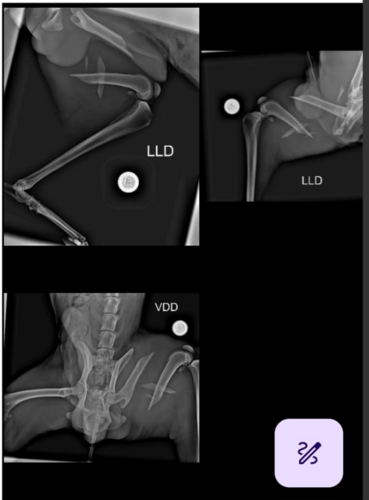

Eu sou o Mauricio Pimenta, e o meu cachorro (TOY) sofreu um acidente e quebrou o fêmur da pata traseira. Ele teve que passar por uma cirurgia e colocou um parafuso na perna. No momento está internado na clinica veterinária Clinivet (Roberto dos Cachorros) que fica em Itaú de Minas. Eu não tenho condições de pagar pelo tratamento e pela cirurgia.